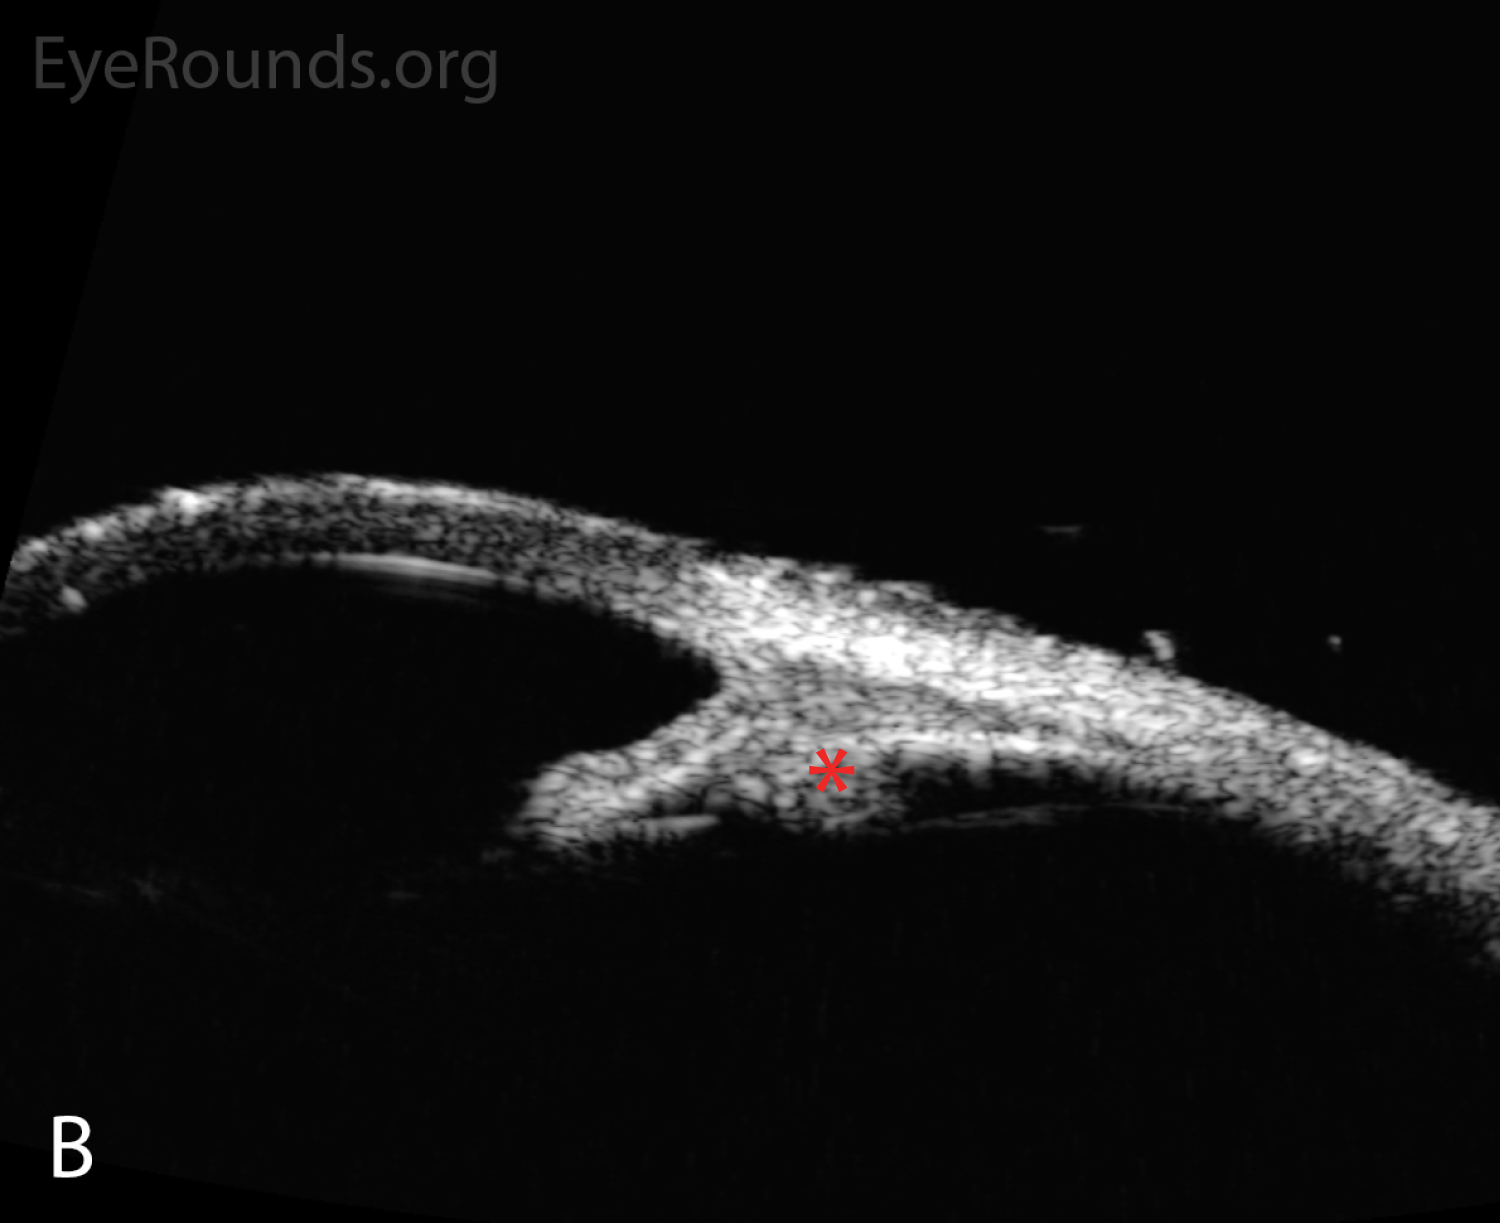

Anterior segment ultrasound of the anterior chamber (A) with attention focused to the ciliary body (B) at two-day follow-up. The anterior chamber is shallow; the angles are narrowed (red angle); the lens-iris diaphragm is displaced forward (red arrow); and the ciliary body is rotated anteriorly (red asterisk). The left eye had a similar appearance. Anterior segment ultrasound of the anterior chamber (A) with attention focused to the ciliary body (B) at two-day follow-up. The anterior chamber is shallow; the angles are narrowed (red angle); the lens-iris diaphragm is displaced forward (red arrow); and the ciliary body is rotated anteriorly (red asterisk). The left eye had a similar appearance.

Figure 2. Anterior segment ultrasound of the anterior chamber (A) with attention focused to the ciliary body (B) at two-day follow-up. The anterior chamber is shallow; the angles are narrowed (red angle); the lens-iris diaphragm is displaced forward (red arrow); and the ciliary body is rotated anteriorly (red asterisk). The left eye had a similar appearance.